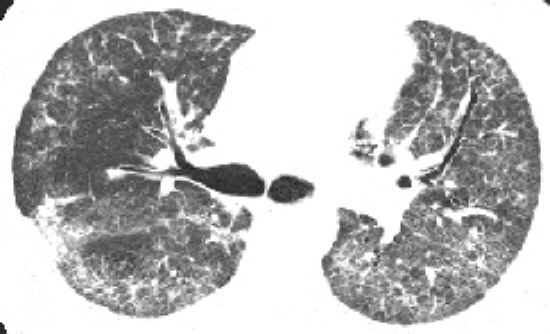

A 鉴别诊断:高分辨CT为试金石

2011版特发性肺纤维化新指南提出,寻常型间质性肺炎的高分辨CT特点可作为独立的特发性肺纤维化诊断手段。这一观点的改变从而使特发性肺纤维化的整个流程发生了巨大变革,高分辨CT在整个诊治过程中都起到了决定性的作用。其中涉及特发性肺纤维化的疾病鉴别也从以前根据临床症状鉴别转而走向以高分辨CT表现为主的鉴别 ......